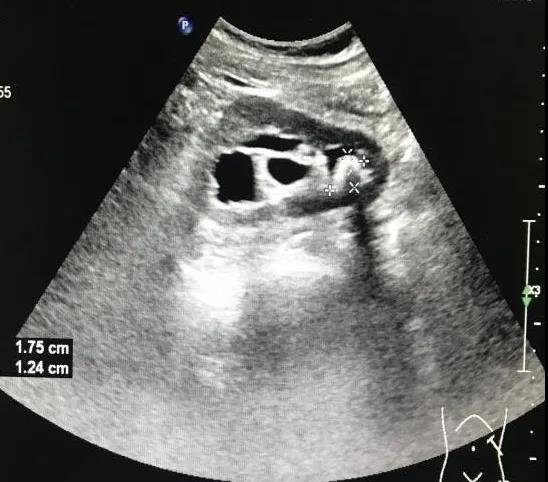

最后我們來(lái)看一個(gè)典型病例。患者男性29歲,打籃球大量飲水1小時(shí)后左側(cè)腰背部突發(fā)劇烈疼痛,為絞痛,同時(shí)伴血尿,急診速來(lái)我院就醫(yī),行泌尿系彩超可見(jiàn)雙腎大小、形態(tài)尚可,被膜尚連續(xù),左腎竇內(nèi)探及一枚強(qiáng)回聲光團(tuán),大小約1.7x1.2cm,后方伴聲影(見(jiàn)圖3),左側(cè)腎盂回聲分離,右側(cè)腎臟未見(jiàn)明顯異常(見(jiàn)圖4)。實(shí)驗(yàn)室尿常規(guī):紅細(xì)胞滿(mǎn)視野,白細(xì)胞2-3/HP,其余陰性。綜合以上考慮為左腎結(jié)石并輕度積水。

圖3:左腎結(jié)石